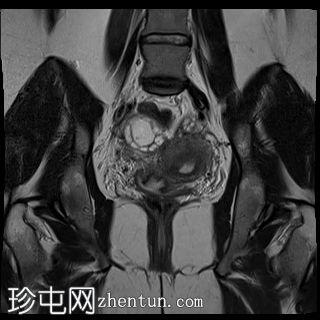

冠状位

T2加权像

双侧卵巢位置接近(卵巢相吻),左侧卵巢内可见一边界清晰的囊性病变,大小约3.1 × 2.7 × 2.9 cm,T1加权像呈高信号,T2加权像可见暗点征及内部暗点征。以上MRI特征符合卵巢子宫内膜异位囊肿的诊断。

右侧卵巢可见一囊肿,大小约为 2.8 × 2.0 × 2.2 cm,T1 加权像呈高信号,囊内可见液-液平面,提示囊内含有不同时期的出血性物质。由于对侧卵巢存在典型的子宫内膜异位囊肿,且该囊肿无强化,影像学表现强烈提示为另一子宫内膜异位囊肿。

双侧卵巢均可见多个小卵泡。